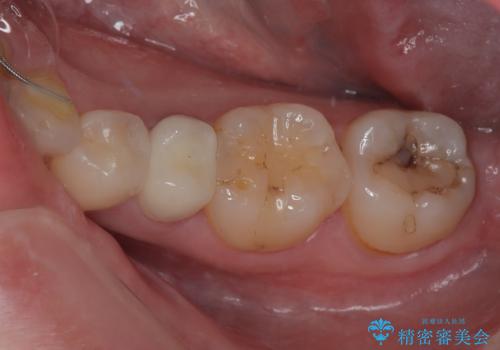

左下が虫歯になっている気がする オールセラミッククラウン

担当医 有澤哲郎